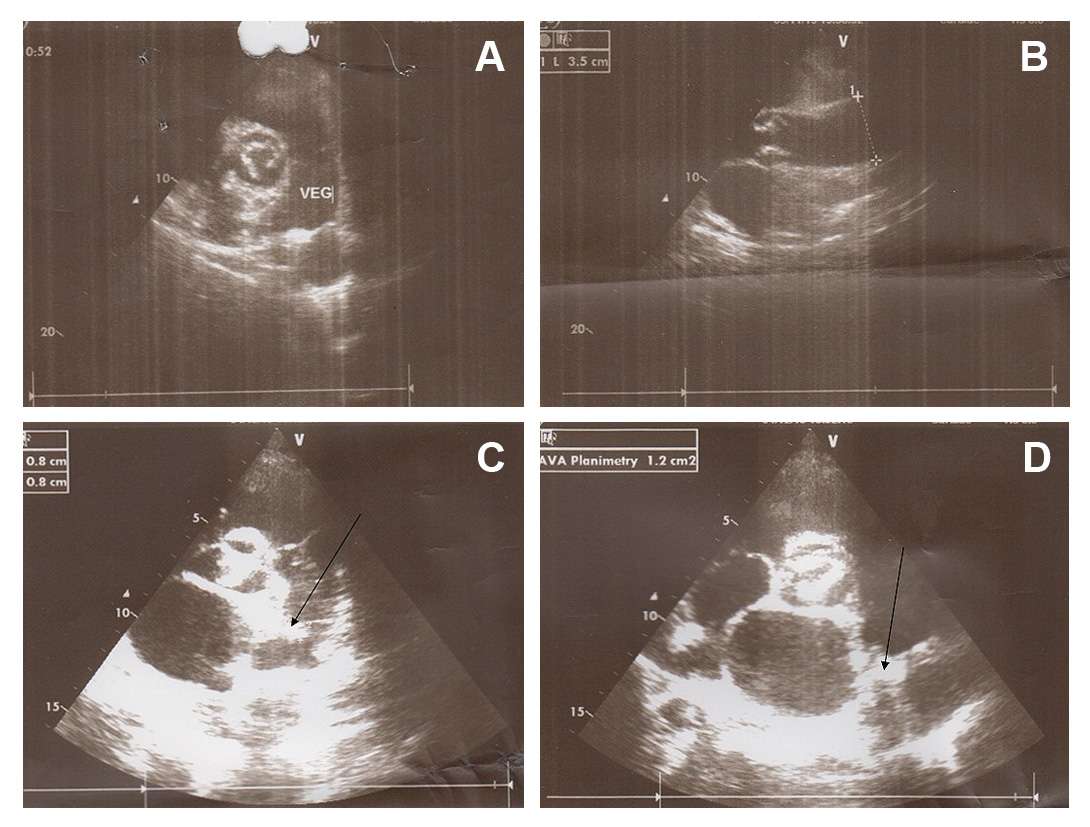

In physical examination, the cardiac examination was not able for prominent grade 3/6 systolic murmurs best heard at the left upper sternal border in second inter costal space with radiation into the anterior left chest. Echocardiogram revealed the presence of a PDA in the setting of normal left ventricular function. However, it had a large diameter but a small shunt was not on TTE echocardiography that caused hemolysis. Transthoracic Echocardiogram showed the left ventricle with conserved systolic function, mild aortic insufficiency with calcified valve, and a fixed structure on the wall of the pulmonary artery with erratic movement indicative of vegetation on orifice of PDA (Figs. 1A and B). Transthoracic Echocardiogram suggested a large (10 mm) PDA with left to right shunt. Pulmonary artery mean pressure was 36 mm Hg, consistent with mild pulmonary hypertension (25-35 mm Hg). Moderate left and right atrial enlargement and a mildly enlarged main pulmonary artery were noted.

Figure 1.

A. Vegetation in PDA extended to main pulmonary artery. B. Concomitant aortic valve calcification with large aortic diameter due to left to right shunt. C. Revealed vegetation in pulmonary side of PDA. D. Shows vegetation in pulmonary side of PDA.

Before admission, she presented with recurrent lung infection that required antibiotic treatment. Chest radiography showed a prominent main pulmonary artery, aorta and haziness on left upper lung field indicating treated septic emboli. Treatment with appropriate antibiotics was started and continued for four weeks. Fever and patents general condition improved with antibiotics but her jaundice was continued (total bilirubin 3.4 mg/dL). After a complete course of antibiotics therapy, laboratory workup showed C-reactive protein 33 mg/L, leukocytes 12,000/mm3, hemoglobin 8.7 g/dL, hematocrit 32%, fragmented red cell on blood smear, negative combs test, which suggested persistent hemolysis despite of recovery from infection. With antibiotic therapy blood cultures became negative for Streptococcus pneumoniae. A hypothesis of hemolysis at PDA tract was confirmed by TEE, which showed large intra luminal vegetation on the main pulmonary artery side of PDA (Figs. 1C and D). With continuation of hemolysis and no regression of intra luminal vegetation, surgical ligation of the PDA was undertaken. The thorax was entered through the fourth intercostal space. The pericardium was opened, and the PDA was identified, dissected, and ligated. After surgical closure of PDA, hemolytic anemia resolved completely after PDA closure. Organized non-mobile vegetation reduced risk of emboli during surgical ligation of PDA. Six month follow up revealed disappearance of jaundice and TEE showed complete closure of PDA with no any shunt.